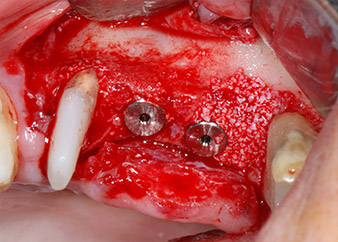

En el siguiente paso, los lechos del implante se prepararon en las posiciones 25 y 26 con instrumentos rotatorios, utilizando un contra-ángulo con un coeficiente de transmisión de 20:1 (WS-75 L, W&H), junto con el nuevo potente motor de implantes Implantmed de W&H (figuras 8 y 19).

A continuación, los implantes (Restore, Keystone Dental, 3,75 mm de diámetro, 8,0 mm de longitud) se colocaron con el motor de implantes (figuras 11 y 12).